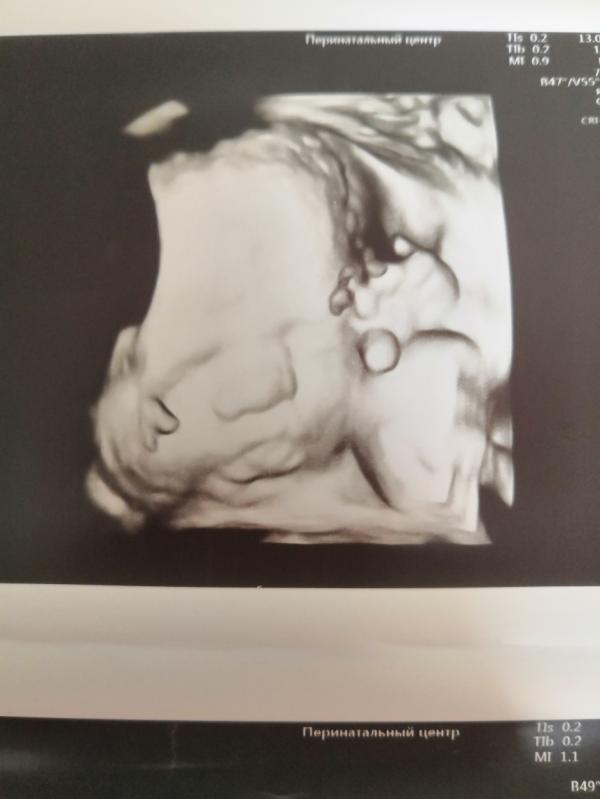

А это сынок в 28,1😍Вес 1172 г

Животик почти на неделю меньше срока, а так все замечательно. Как истинный пацан-сидит на корточках 😂